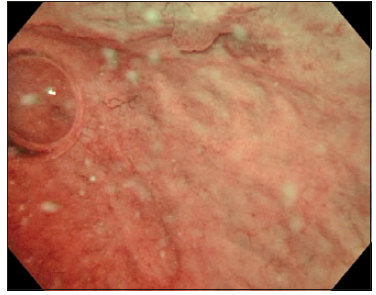

When there is a bleeding, the whole field of view becomes colored and unclear because NBI light bands are easily absorbed by hemoglobin (Fig. 6). Therefore, special attention is required during insertion of the cystoscope to avoid bleeding due to manipulation.

Fig. 6. NBI observations. (A) Bleeding from prostatic urethra by cystoscopic manipulation (posterior part is the bladder neck).

Fig. 6. NBI observations. (B) Inside the bladder. Bleeding makes the field of view dark and unclear.